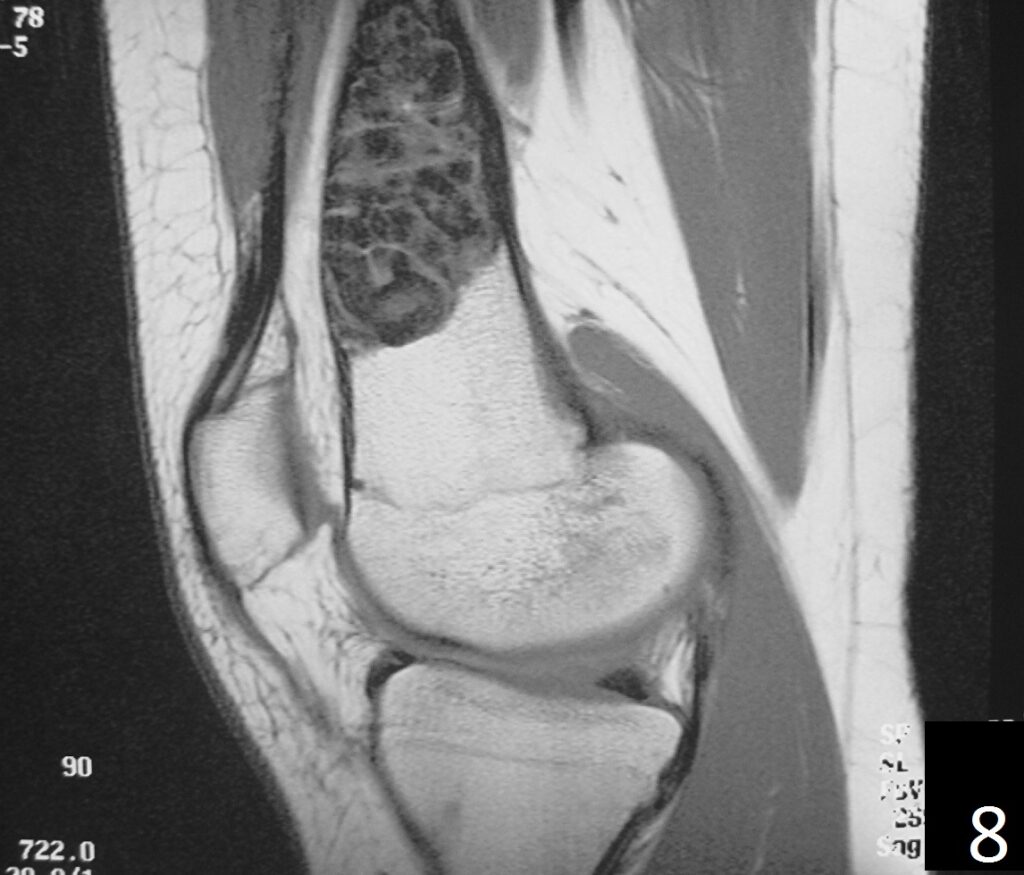

MRI

• Low- signal on T1 (Fig. 8)

• Variable heterogeneneous signal on T2 (Fig. 9).

• Possible extensive hypercellular fibrous tissue and hemosiderin seen on T2

Fig. 6-9: Sagittal T1 (Fig. 6) and T2 (Fig. 7) MRI of the knee demonstrates a fibrous cortical defect. Axial T1W (Fig. 8) and T2W (Fig. 9) show a heterogeneous lesion on distal femur, compatible with nonossifying fibroma.